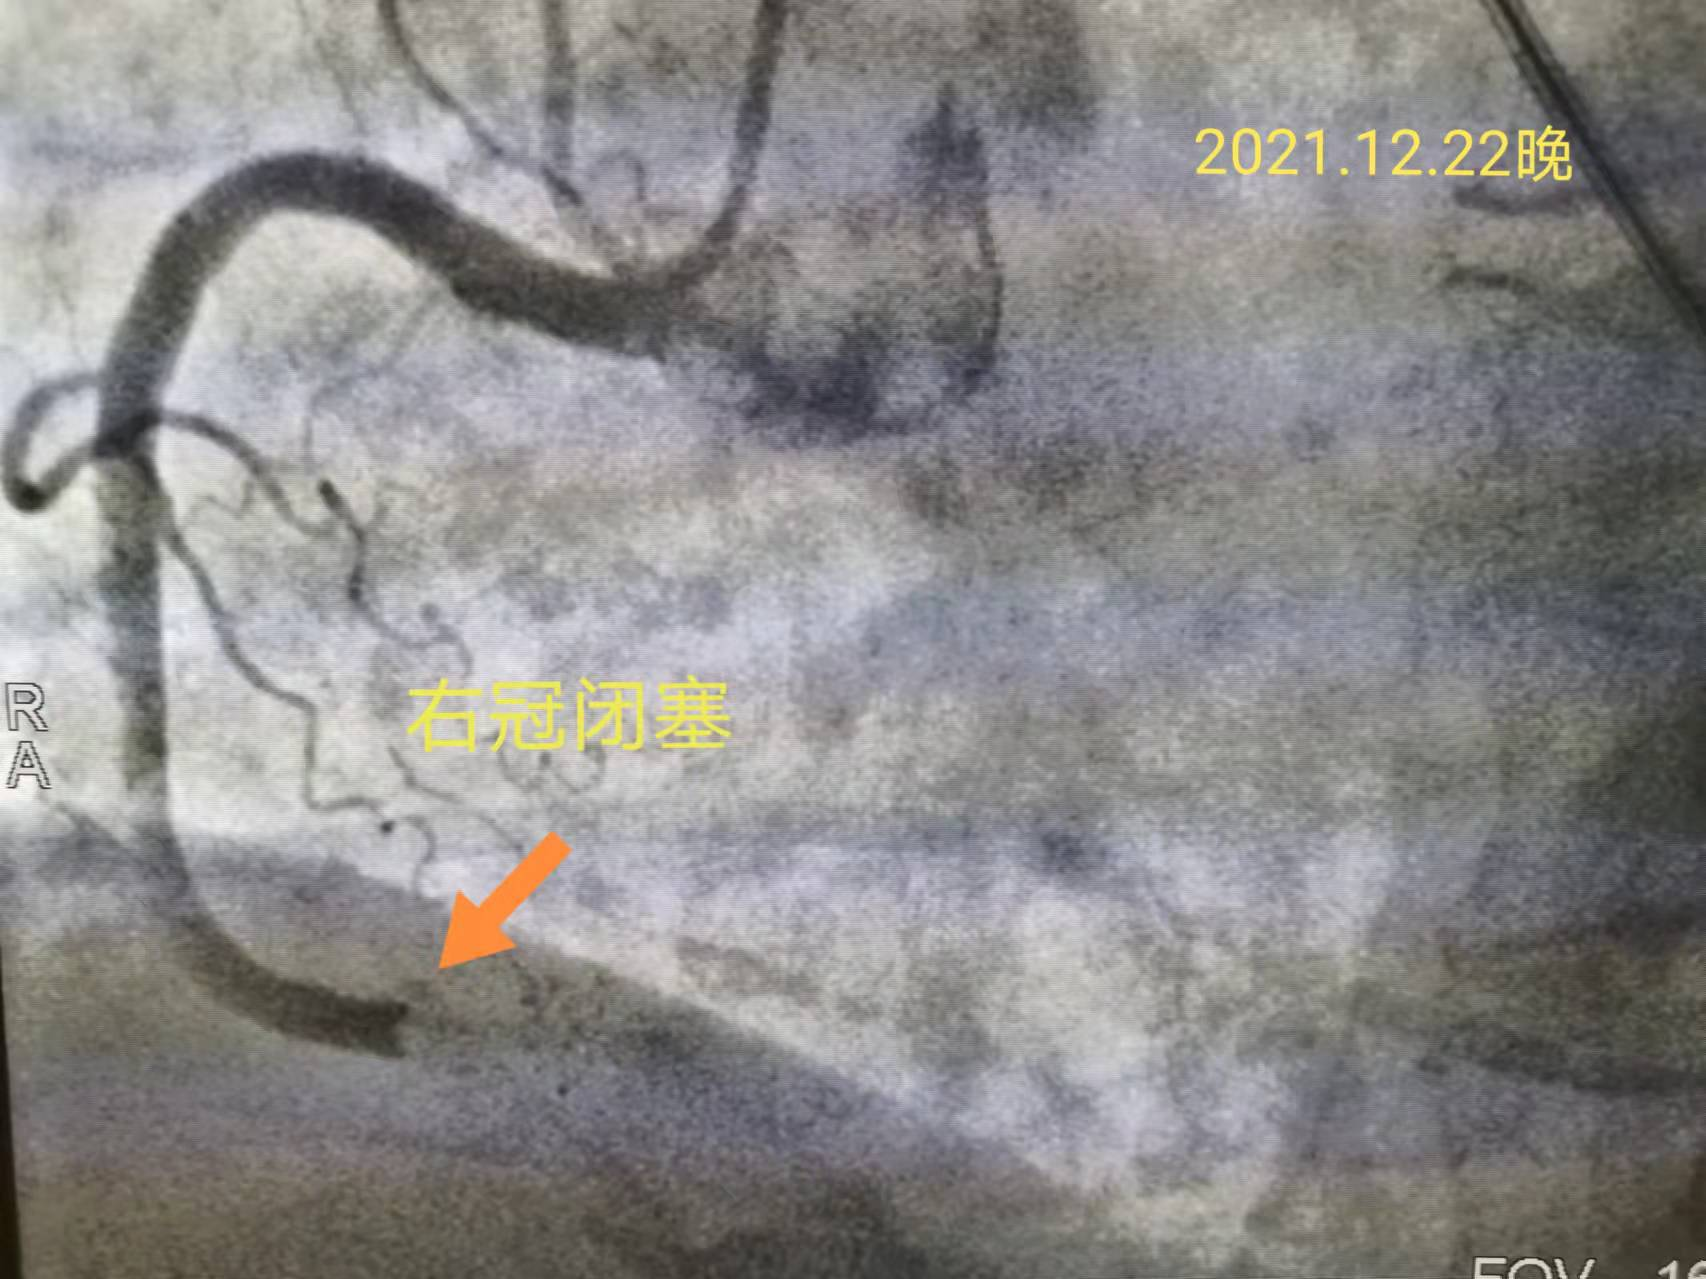

23时50分,急诊PCI手术开始了。邹医生按照急性心肌梗死救治流程,快速完成冠状动脉造影,通过导丝行球囊扩张及支架植入,孙大娘被堵塞的右冠状动脉开通了。之后重复造影显示原狭窄部位消失,远端血流TIMI 3级。从患者进入医院大门就诊到球囊扩张后血流恢复,门球时间不到30分钟!(门球时间国际标准90分钟,门球时间每延长15分钟,死亡率将明显升高)。这个数字充分彰显出我院心脏介入团队的实力!